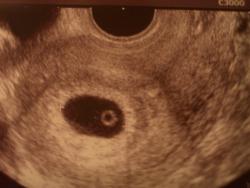

10月15日に心拍確認のために病院へ行きました。

6週1日目(10月15日)

無事に心拍が確認出来ました!

チカチカと凄いスピードで光ってました。

fukuro

胎のうは19.3mmと育ってくれていました。

赤ちゃんはまだ3.5mmの大きさだそうです。

一応先生に「順調です」とお言葉を頂き少し一安心。